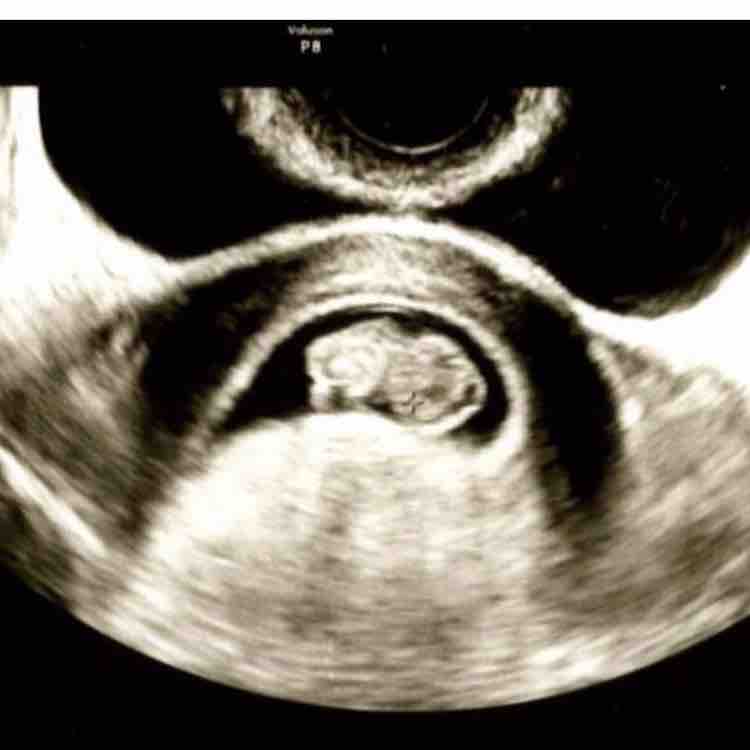

胎嚢 たいのう とは 大きさや形は 妊娠初期に確認できないとどうなる Cozre コズレ 子育てマガジン

胎嚢 画像 実物-保有機器のご紹介 シミュレーションセンターが保有している機器の一部をご紹介します。 全機器、備品については、こちらの機器一覧をご覧下さい。 ・「MICS僧房弁シミュレータMX1」が増えました。 (21年度導入) ・「動脈穿刺モデル」5台に加えカテゴリー移しました! 今日は胎嚢確認してきました(^^) 最後に画像貼ります! 4w6dとのことで、12ミリでした☆ hcgは9000オーバー(゚ω゚;) もしかしたら前回の数値はあまりにも高すぎるから小数点が見えなかったのかもしれない!と思ってましたが、今日見たのは確実に9000超えてたし、前回の

妊娠日数と妊娠画像 実際の妊娠画像を妊娠日数とともに確認します。 18~21日:胎嚢が認められるようになります。発現時期 は個体によって異なり、径も小さいため、早い時期での妊娠 診断はかなりの技術が必要です。 図5は、妊娠19日目の画像です。

妊娠5週目 胎嚢の大きさ エコー写真 つわり症状や流産のこと 妊娠初期 All About